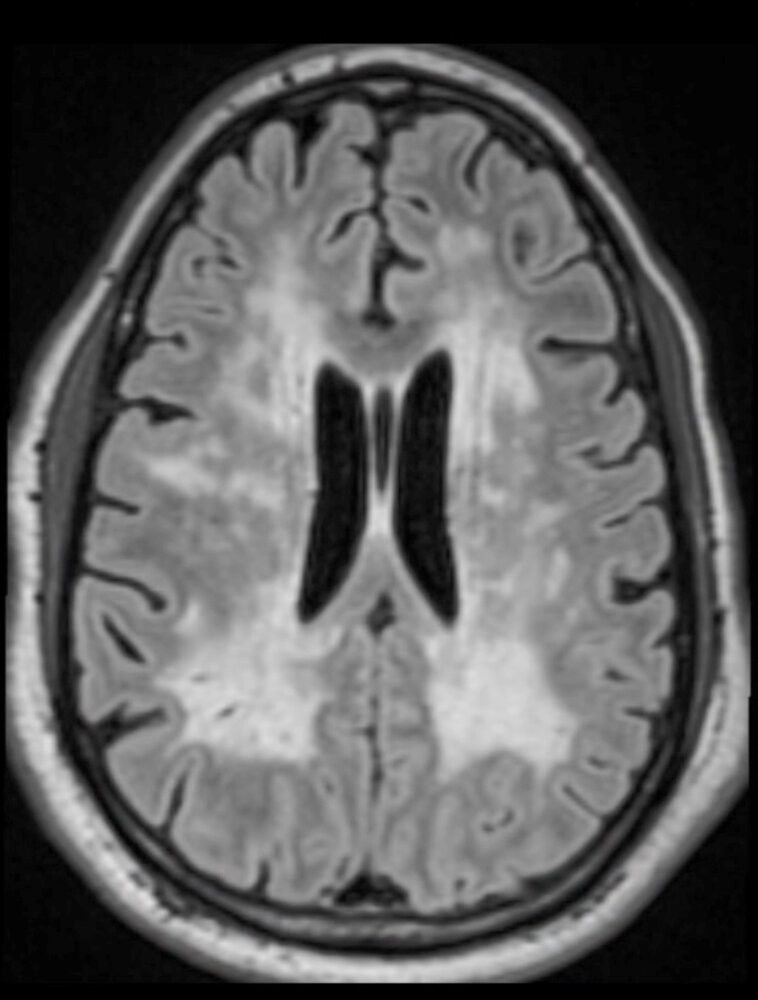

Vascular dementia. MRI or CT shows multiple cortical and/or subcortical infarcts and prominent sulci:

(^MRI)